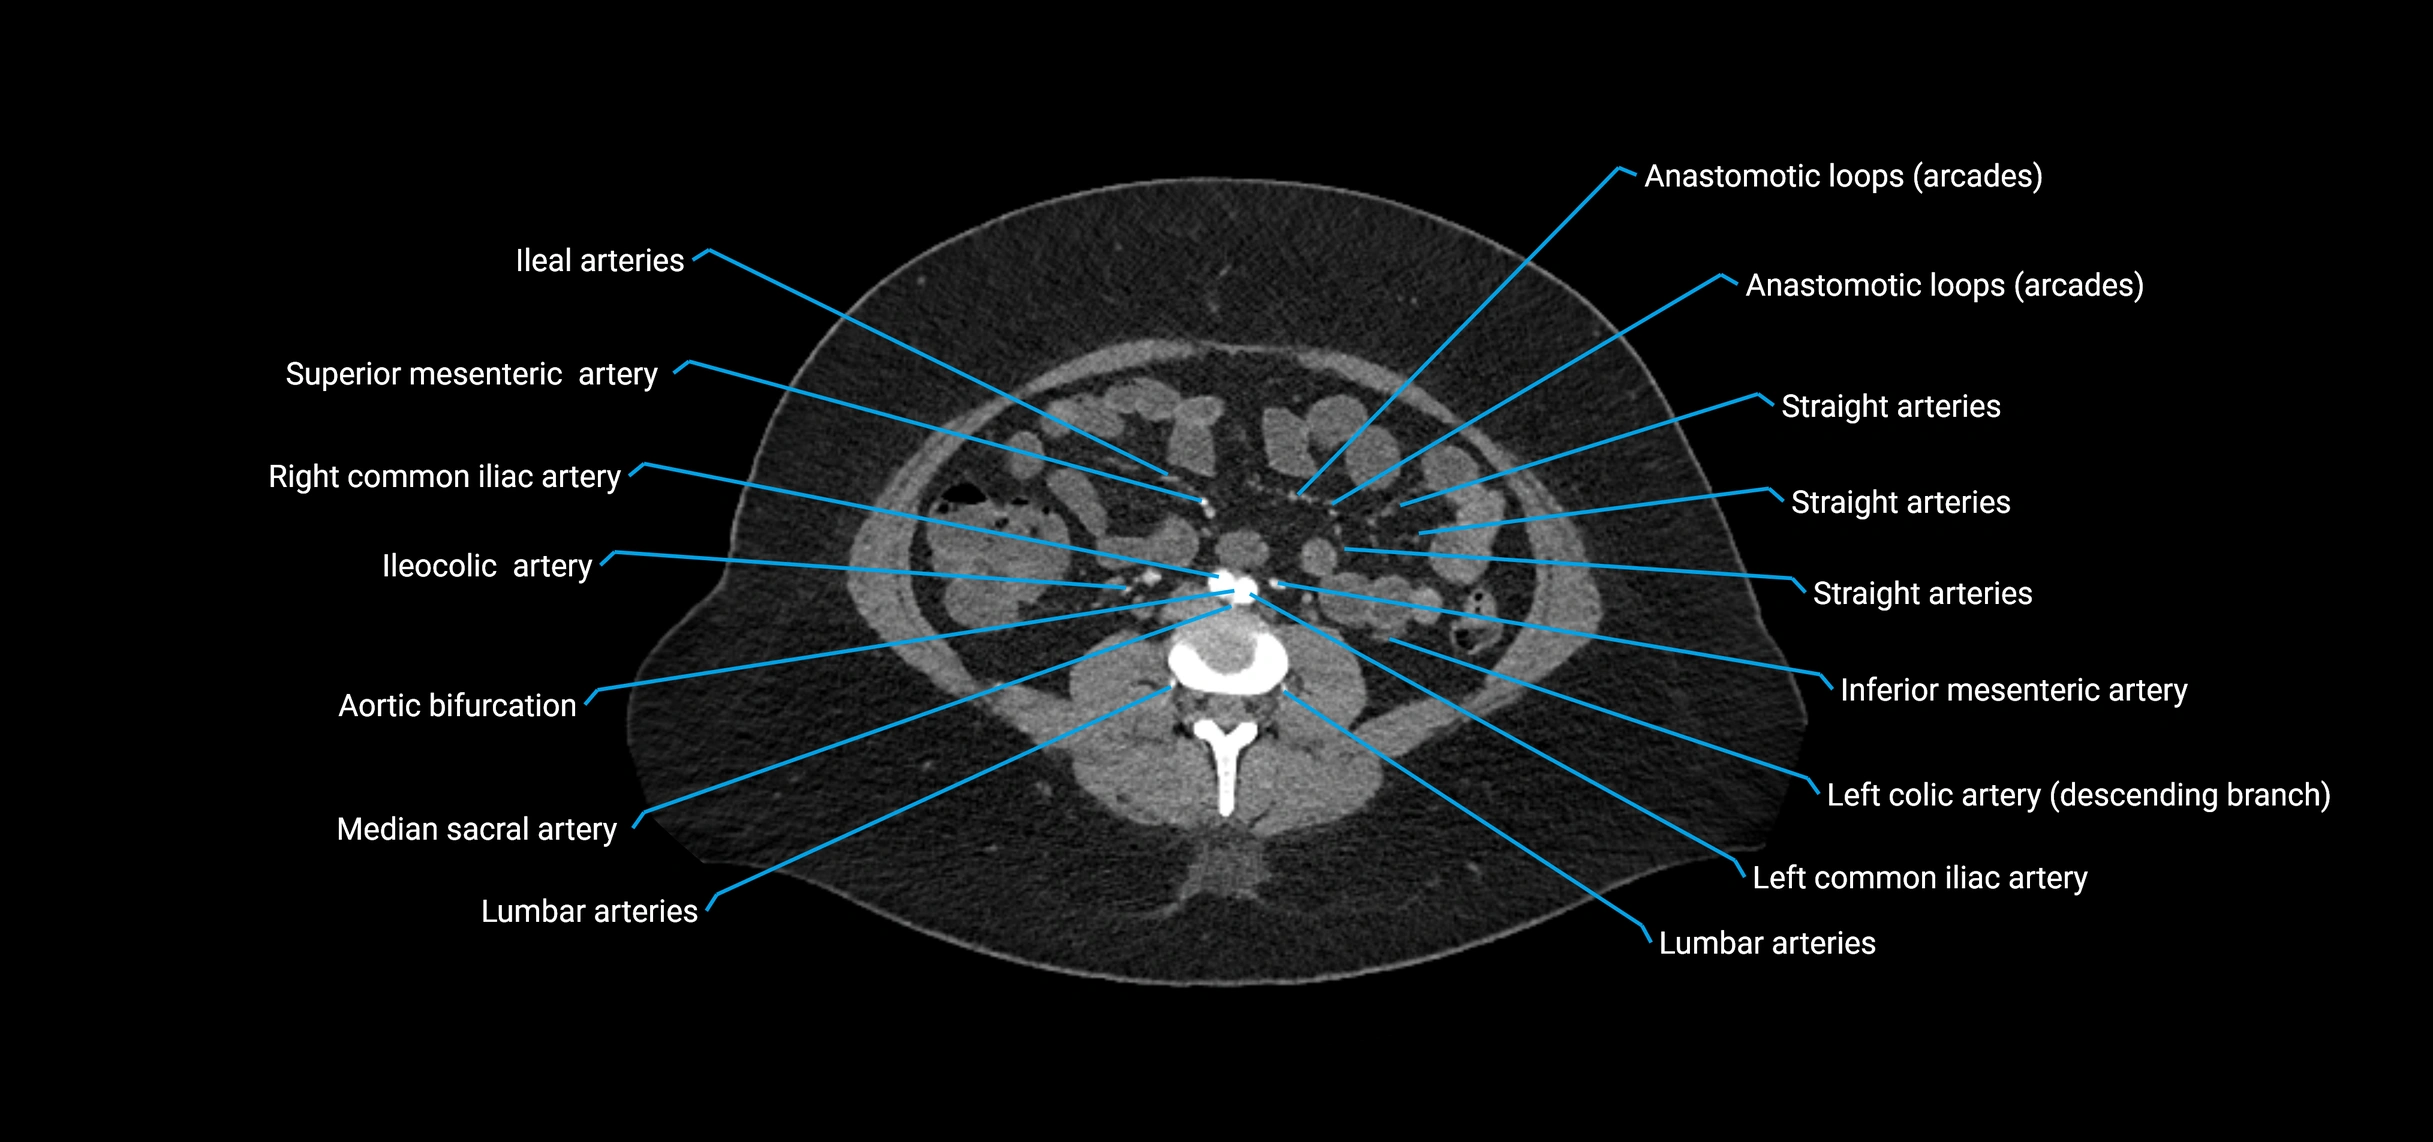

CT images

image

CT Appearance

Non-contrast CT:

• Appears as a tubular soft tissue structure anterior to vertebral bodies

• Calcified atherosclerotic plaques appear as hyperdense foci along the wall

• Useful for screening abdominal aortic aneurysm (AAA) size and mural calcification

Contrast-enhanced CT (CTA):

• Gold standard for abdominal aortic imaging

• Provides excellent detail of lumen, wall, aneurysm, thrombus, and branch vessels

• Multiplanar and 3D reconstructions help in aneurysm measurement, stent graft planning, and dissection evaluation

• Detects acute rupture, traumatic injury, or occlusion with high sensitivity

The abdominal aorta is the continuation of the thoracic aorta, beginning at the level of the aortic hiatus of the diaphragm (T12 vertebra) and terminating at the level of the L4 vertebra where it bifurcates into the right and left common iliac arteries. It lies slightly to the left of the midline and courses anterior to the vertebral bodies, surrounded by the retroperitoneal structures of the abdomen.

The abdominal aorta gives off numerous visceral and parietal branches, supplying the abdominal organs, pelvic structures, and lower limbs. It is the main conduit of oxygenated blood from the heart to the abdomen and lower body. The aorta is clinically significant as the common site of aneurysm, dissection, atherosclerosis, and traumatic injury.

• Unpaired visceral branches: celiac trunk, superior mesenteric artery (SMA), inferior mesenteric artery (IMA)

• Paired visceral branches: middle suprarenal arteries, renal arteries, gonadal arteries (testicular or ovarian)

• Parietal branches: inferior phrenic arteries, lumbar arteries, median sacral artery

• Terminal branches: right and left common iliac arteries